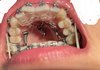

교정이 너무 힘든데 어카지